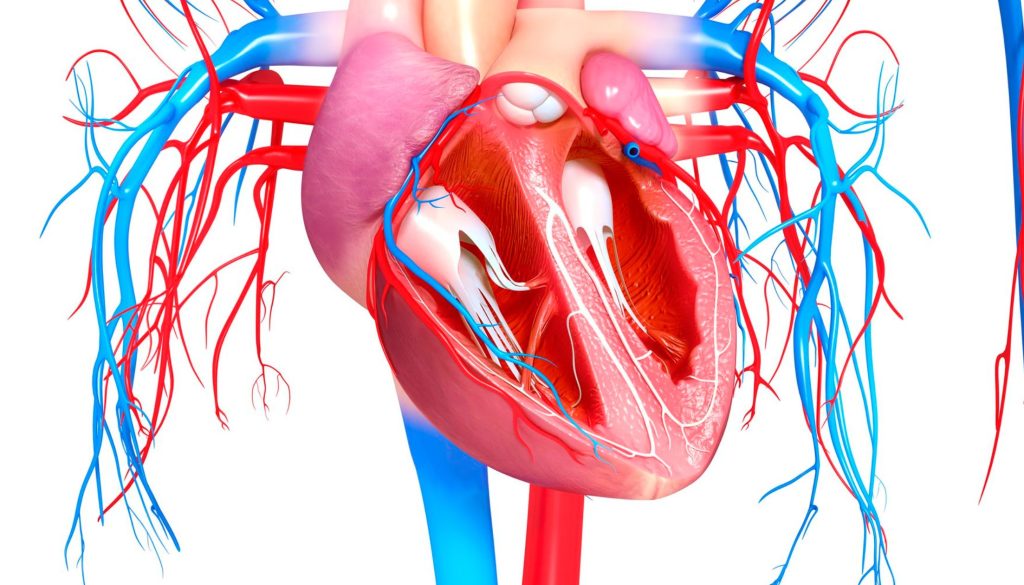

توسيع صمامات القلب أو ما يعرف طبيًا بعملية “تَكبير الصمام” يهدف إلى علاج ضيق الصمامات القلبية، الذي يمكن أن يمنع تدفق الدم بشكل كافٍ، مما يؤدي إلى إجهاد القلب وزيادة مخاطر حدوث مضاعفات صحية أخرى. تتم هذه العملية غالبًا باستخدام تقنية القسطرة القلبية أو من خلال الجراحة التقليدية، وذلك بناءً على شدة المشكلة وحالة المريض الصحية.

1. **القسطرة البالونية**

تعد القسطرة البالونية إجراءً شائعًا يعتمد على إدخال بالون صغير عبر القسطرة إلى الصمام المتضيق، ثم نفخه لتوسيع الصمام. هذه الطريقة تُعتبر بشكل عام أقل توغلاً من الجراحة التقليدية، وتستخدم بشكل خاص للمرضى الذين لا يتحملون الجراحة المفتوحة.

2. **جراحة الصمام المفتوح**

تتم هذه العملية عبر فتح الصدر واستبدال أو إصلاح الصمام المتضيق. تستخدم هذه الطريقة في حالة وجود ضرر كبير في الصمام أو عندما لا تكون القسطرة البالونية فعّالة.

3. **استبدال الصمام عبر القسطرة (TAVR)**

هذا الإجراء هو خيار متاح للمصابين بضيق الشريان الأورطي ويعتمد على إدخال صمام بديل عبر القسطرة دون الحاجة إلى جراحة مفتوحة.